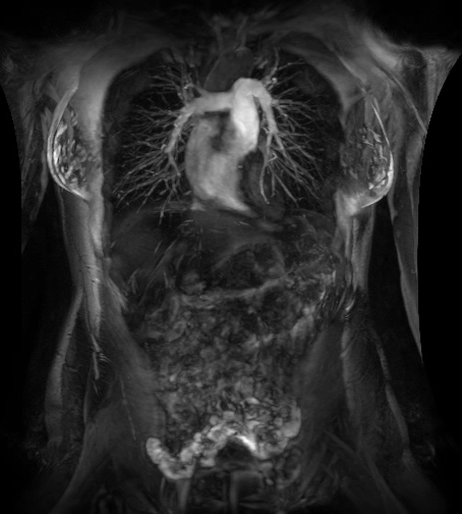

在乳腺MR檢查中,SIGNAWorks?通過可調節(jié)線圈元件使得乳腺成像實現(xiàn)定量化和個性化,從而實現(xiàn)精準醫(yī)療。創(chuàng)新型應用——用于超快速動態(tài)掃描的DISCO,用于高分辨率形態(tài)成像的Cube T2 with HyperSense和Cube T2 HyperCube,縮短了掃描時間并促進了擴散技術(Focus和MUSE)的發(fā)展,利用與BIRADs一致的CADStream來探測組織特征和分析。